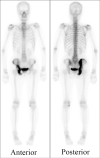

Incidentally Discovered Paget's Disease of Bone

Keywords: Paget's disease of bone; alkaline phosphatase; bone scintigraphy; computed tomography.